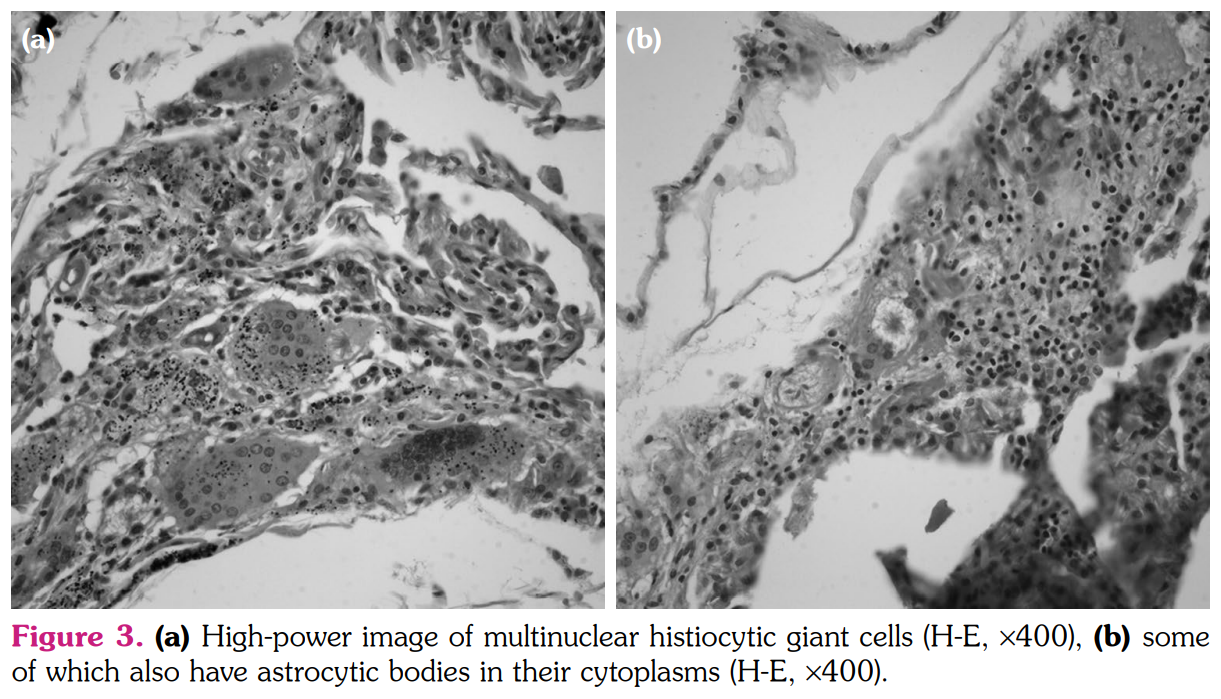

The smears of bronchoalveolar lavage (BAL) were negative for any bacteria, fungi, or acid- fast bacilli. Cytological examination revealed numerous macrophages, few lymphocytes, and few neutrophils. BAL cultures were also negative. Serological tests for the infection of viruses and fungi were negative. The pathological examination of pulmonary wedge resection performed from lingula revealed foreign-body type giant cell reaction and poorly- formed non-caseating granulomas distributed mainly along interlobular septa and subpleural zones (Figure 2). Asteroid bodies as well as a birefringent material were seen in the cytoplasms of giant-cell histiocytes under polarized microscope (Figure 3a, b). Histochemical stains did not reveal any microorganisms and lung tissue cultures were also negative for any mycobacteria species. Based on the clinical, radiological, and pathological findings, a diagnosis of sarcoid-like granulomatous reaction induced by adalimumab was confirmed. Given the lack of radiological response four months after cessation of adalimumab, methylprednisolone 32 mg/day peroral was initiated. The patient was controlled every month initially and every two months thereafter with a gradual reduction in methylprednisolone dosage. At the end of nine months of steroid therapy, a control CT of thorax revealed stable nodular opacities in both lungs. As psoriatic lesions gradually increased and worsened during this period, ustekinumab was started.